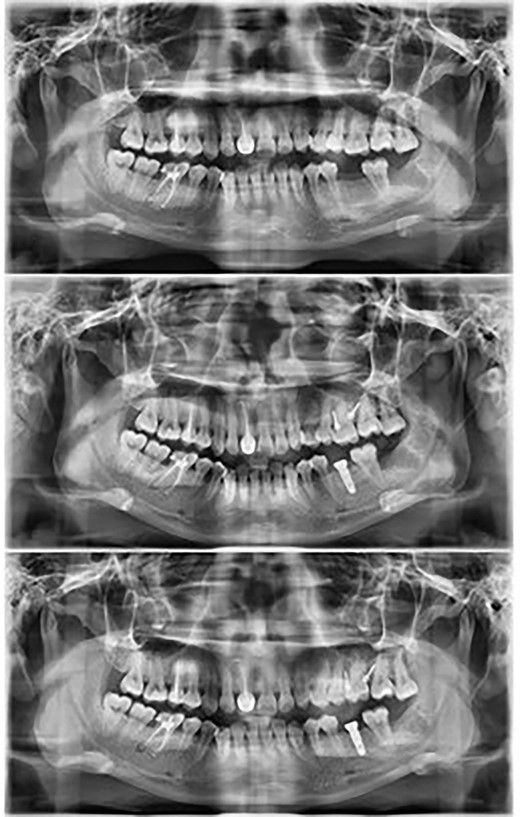

Allowed for placement of full coverage crown on the implant placed to replace the mandibular first molar (Fig. 4).

Full coverage crown placed on the implant to replace the mandibular first molar.

From the panoramic radiographs, it can be visualized that there was no observable resorption and the molar easily intruded into the floor of the nasal cavity without any resorption [9]. To minimize the possibility of relapse, the patient was delivered clear vacuum formed retainers for the upper arch while the opposing tooth would receive a full coverage crown on the implant to achieve good occlusion.